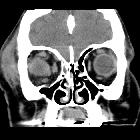

orbital blowout fracture

Orbital blowout fractures occur when there is a fracture of one of the walls of orbit but the orbital rim remains intact. This is typically caused by a direct blow to the central orbit from a fist or ball.

Inferior blowout fracture

Inferior blowout fractures are the most common. Orbital fat prolapses into the maxillary sinus and may be joined by prolapse of the inferior rectus muscle. In children, the fracture may spring back into place (see trapdoor fracture). Most fractures occur in the floor posterior and medial to the infraorbital groove .

CT

CT is the modality of choice for assessment of the facial skeleton. A full assessment does not require the administration of contrast. Ideally, the acquisition should be performed using the thinnest detector settings, enabling thin-slice reconstructions along three orthogonal planes with a bone algorithm. Additional soft tissue algorithm reconstructions using larger slice thickness and 3D volumetric reconstruction are useful for assessing associated soft tissue injury and gauging facial asymmetry, respectively.